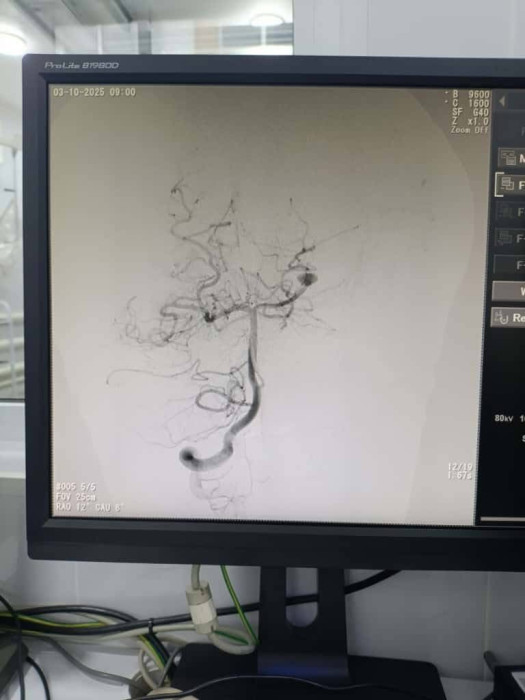

Улуттук госпиталдын базасында мээнин оор кан тамыр ооруларына, башкача айтканда, аневризма жана артериовеноздук мальформацияга (АВМ) чалдыккан балдарга жогорку технологиялуу эндоваскулярдык операциялар ийгиликтүү жүргүзүлдү. Бул тууралуу бүгүн, 13-октябрда Саламаттык сактоо министрлигинин басма сөз кызматы билдирди.

"Операциялар заманбап ангиографиялык операциялык бөлмөдө, интраоперациялык визуалдаштыруунун эң жаңы ыкмалары колдонулган шартта өттү. Мультидисциплинардык командага эндоваскулярдык нейрохирургдар, анестезиолог-реаниматологдор, рентген-лаборанттар жана жандандыруу бөлүмүнүн дарыгерлери кирди. Мындай ыкма жогорку деңгээлдеги коопсуздукту, так диагностика жана дарылоонун натыйжалуулугун камсыз кылды", - деп белгиленди маалыматта.

Кошумчалангандай, ага чейин кан тамырлардын анатомиялык өзгөчөлүктөрүн, патологиялык түзүлүштөрдүн көлөмүн жана жайгашкан жерин аныктоо максатында деталдаштырылган ангиографиялык диагностика жүргүзүлдү. Адистер коллегиалдык талкуулоодон кийин ар бир бейтап үчүн оптималдуу дарылоо тактикасын тандашты.